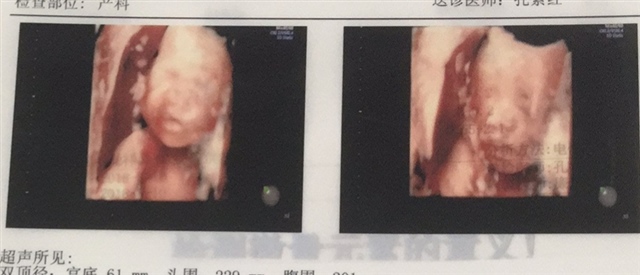

孕13周+4天

孕16周+5天